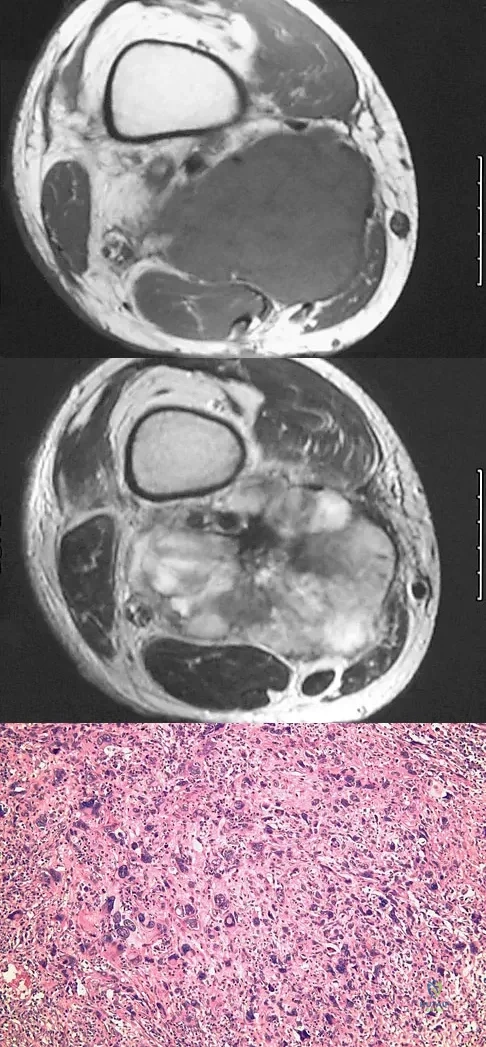

A 37-year-old man pulled his hamstring playing softball 3 weeks ago. The patient had not noted any mass prior to his injury. MRI scans of the posterior thigh are shown in Figures 4a and 4b. Figure 4c shows the biopsy specimen from a needle biopsy. What is the most likely diagnosis?

Explanation

A healthy 16-year-old boy has had increasing pain in the right knee for the past 3 months. Examination reveals warmth and swelling around the distal femur. Radiographs and an MRI scan are shown in Figures 51a through 51c, and a biopsy specimen is shown in Figure 51d. What is the most likely diagnosis?

Explanation